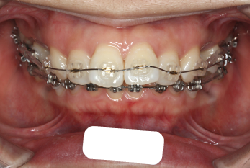

「歯並びの凸凹を直したい」という主訴で来院したケースです。診断の結果、たしかに「叢生」という隙間が足りないと言うことが原因の凸凹症例でした。

しかし、それ以上に問題なのは「前歯の噛み合い方が深すぎる」という症状で、初診の歯の正面写真を見ると下の前歯が全く見えません。こういう症状を矯正学では「過蓋咬合(かがいこうごう)」と言います。過蓋咬合を放置すると、将来的に顎関節に悪影響を与えるとされており、顎関節症の原因因子の一つです。また下の前歯の先端が、上の前歯の裏側の歯茎と強く接触するため、歯周病の原因にもなります。

検査の結果、凸凹が軽症なため非抜歯で矯正すること可能と判断、マルチブラケット装置にて治療しました。治療後は歯並びが綺麗になっただけでなく、噛み合わせ的にも正しい状態が確立しています。